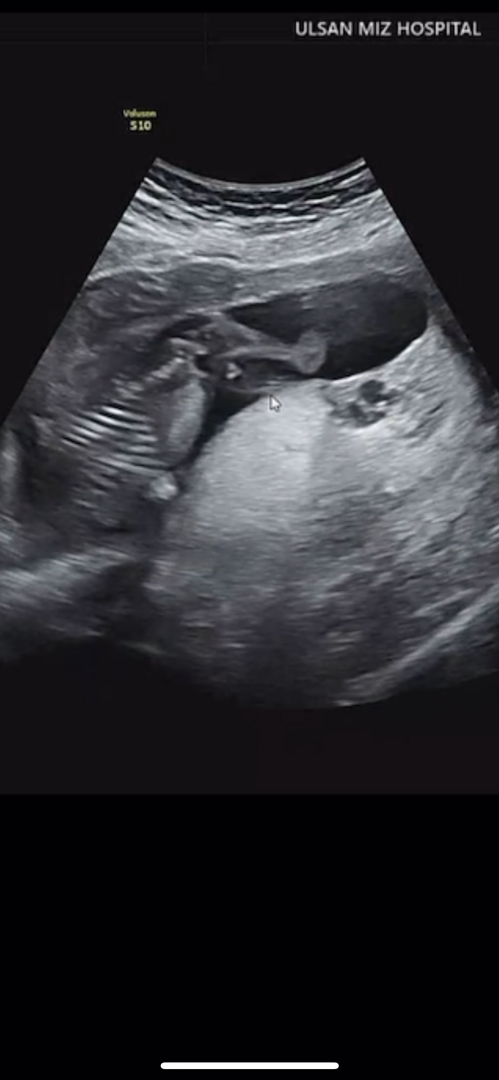

저 아들 확정이에요...

어제 성별 반전 열심히 검색했지만.. 저 동그라미 세개는 누가봐도 아들이겠죠...ㅠㅠ 남편과 저 둘다 딸 원했는데 바라던 딸이 아니라서 기운이 나진 않네요.. 하하... 주변 아들맘이 아주 큰 장점은 목욕이나 워터파크 갈 때 제가 씻길 일 없다는거라고 하던데 ㅠㅠ 다른 장점도 있을까요??